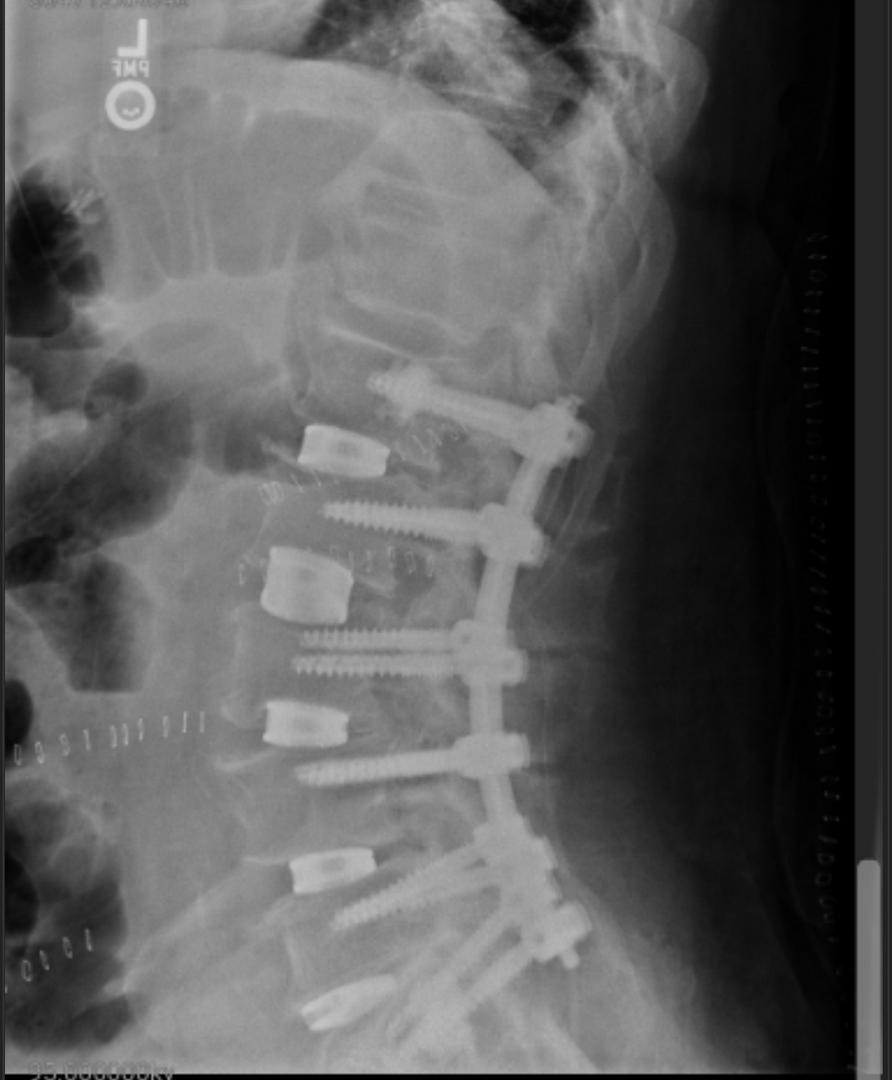

Those vertebrae are being crushed little, by little, by little, paydays coming. Ask me how I know.

I have had 2 back surgeries believe doctors will let you suffer these days please dont do that

Heck ya, I never did anything quite like that, but I hurt my back in the service working dumb, but under orders. Lamenectomy, and a spinal fusion, couldn't put me together again. You know, I am 75 and tied to my wheelchair and walker, and I wish like heck, I could lift just one of those boards and take even one step with it.😲 Do it while you're young, but be smart about it. Smarter than that guy anyway.🤔 Besides, no boss is going to want to see that. Injuries cost everyone money!